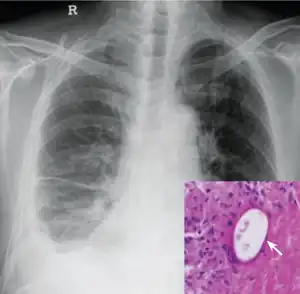

Infection

Symptoms of paragonimiasis may include abdominal pain, diarrhea, fever, and hives. If the infection remains untreated, the symptoms may diminish or disappear after only few months, but sometimes they last for decades.[6] Paragonimiasis is caused by the body's natural immune response to the worms and eggs that are present and also migrating from the intestines to the lungs.

As a rule, the parasites begin to cause symptoms about three weeks after ingesting live metacercariae. After about eight weeks, they begin to produce eggs in the lungs. Some patients develop brain damage if parasites establish in the brain and produce eggs. The brain damage commonly causes headache, vomiting, and seizures.[4] Untreated cerebral paragonimaisis commonly results in death from increased intracranial pressure.